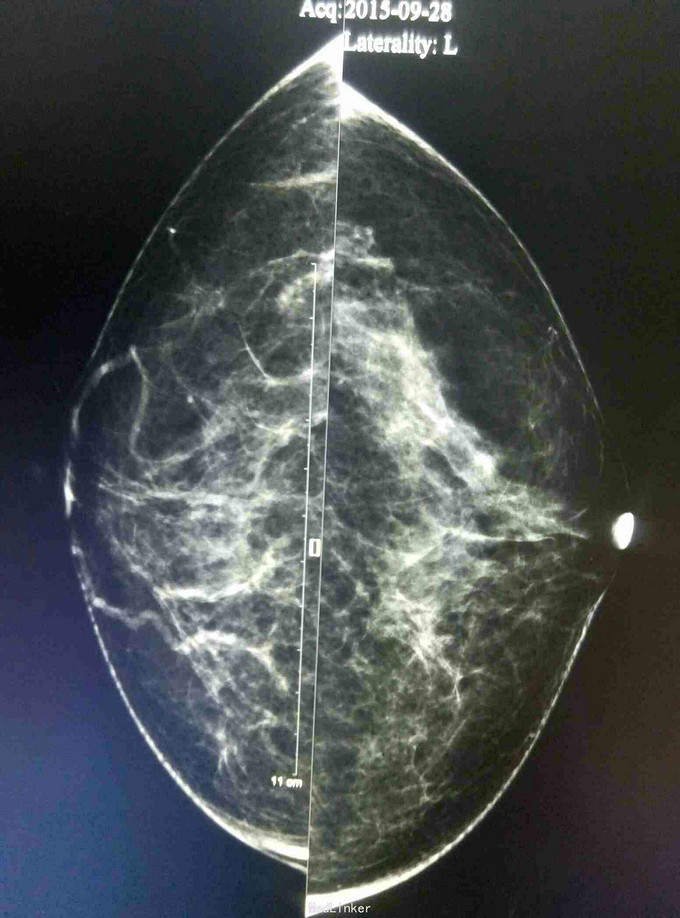

患者,女,50岁,体检发现右乳肿物1月

查体:体格检查未触及明显肿物 辅助检查:彩超钼靶如图所示

诊断:右乳纤维瘤? 治疗:局麻下行右乳肿物切除活检术,术后病理示:右乳肿物符合血管肉瘤样变。经汇报讨论,采取全乳切除加腋窝淋巴结清扫,术后可考虑放疗。